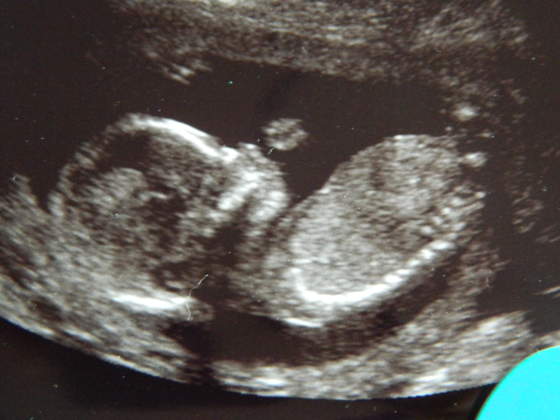

Kruszki, piękne zdjęciaA znacie płeć? Bo mi na dziewczynkę wygląda - tak po twarzy

hehehe no to zescie teraz napisalykruszki piękne małe słoneczko, a mnie na chłopczyka wyglądahihi